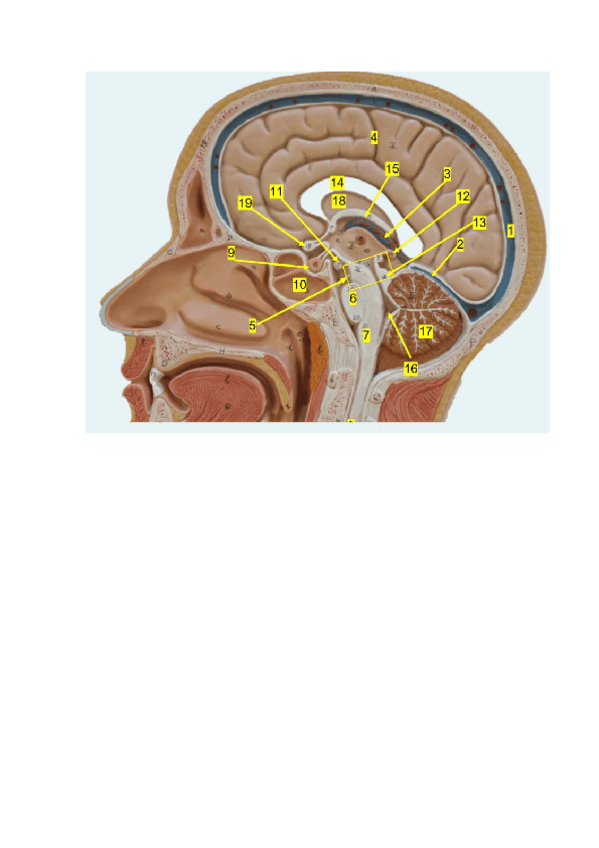

Si sabes rotular las estructuras de estas imágenes tienes el práctico hecho.